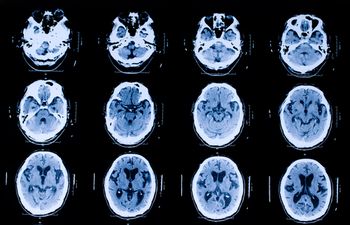

PET with [18 F]flutemetamol can assist physicians in early and more accurate diagnosis of early onset dementia.

Brain PET and age may help clinicians determine which patients with amnestic mild cognitive disorder may progress on to probable Alzheimer’s disease.